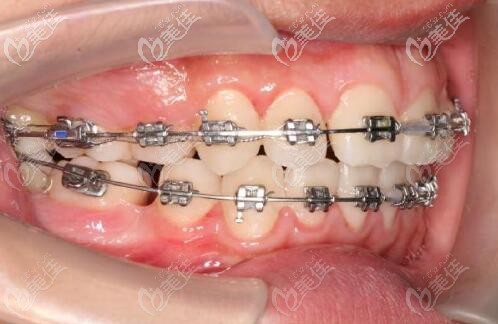

戴上鋼牙套

對(duì)于牙套,高醫(yī)生推薦了自鎖,因?yàn)槟Σ亮π?,矯正的也快一些,加上小孩子自制力,比較差,戴隱形牙套如果不自律很影響效果。